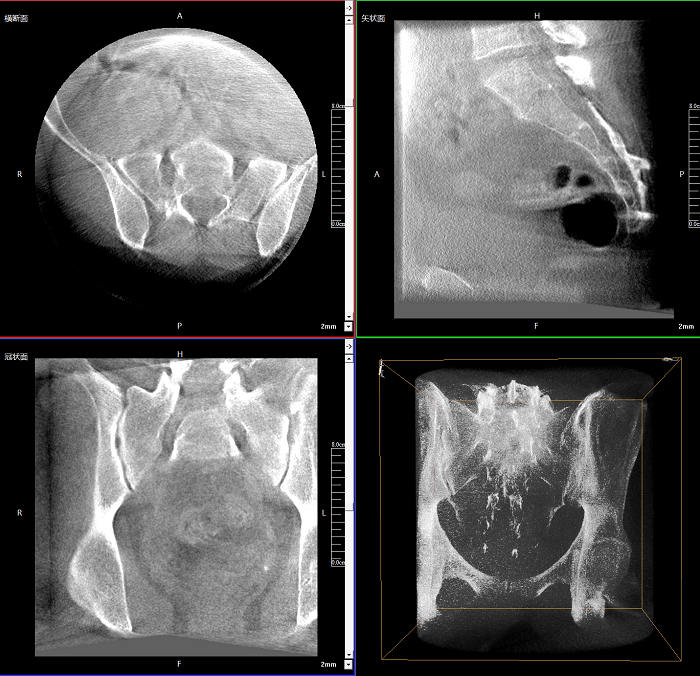

該設備可進行快速的術中三維掃描,生成類CT斷層圖像和立體3D圖像,保障植入物置入效果。廣泛適用于骨科、脊柱外科、矯形外科、創傷骨科等其他領域。

術中實時生成橫斷面、矢狀面、冠狀面及三維影像,可在任意切面、任意角度評估植入物和解剖結構的相對位置。

術中CT檢查 減少翻修概率

通過術中三維影像的檢查,可以立即發現植入物的錯位,減少不必要的第二次手術,減少并發癥概率以及感染風險。